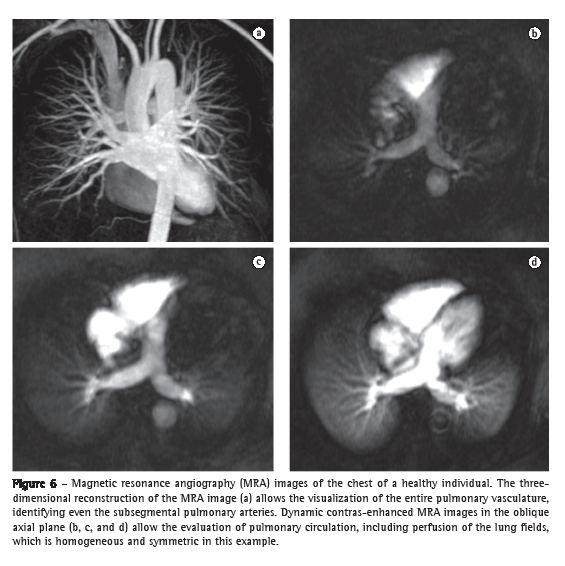

Pulmonary circulationBy means of the new MRA techniques, principally the use of gadolinium-enhanced 3D GE sequences, it is now possible to identify even the fourth-order subsegmental pulmonary arteries of a normal lung. This technique allows the acquisition of images of high temporal resolution every 1.0-1.5 s, and these images can also be used to study lung parenchyma perfusion (Figure 6).(40) The GE sequences that show blood flow with high signal intensity, also known as bright blood sequences (balanced GE sequences, cine MRI, and cine phase-contrast MRI) allow the evaluation of the large blood vessels of the thorax without the need for contrast use, as well as allowing the dynamic evaluation of and flow measurement in the pulmonary arteries and aorta, thereby providing functional information for use in morphological studies.(41)

In the characterization of central lung cancer with obstructive pneumonia or atelectasis, MRI is useful and differentiates a tumor mass from secondary changes, which present increased signal intensity on T2-weighted images and a more homogeneous appearance (due to the accumulation of secretions and fluid), as well as an enhancement pattern that is different from that of the neoplastic lesion.(34) In invasive pulmonary aspergillosis, MRI is more specific than CT in characterizing consolidations associated with hemorrhagic infarction secondary to vascular invasion (Figure 4).